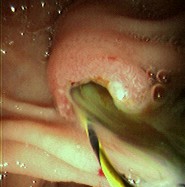

Acute cholangitis

Endoscopic photo of same patient following removal of large common bile duct (CBD) stone; note copious pus draining through the ampulla

From the collection of Douglas G. Adler; used with permission